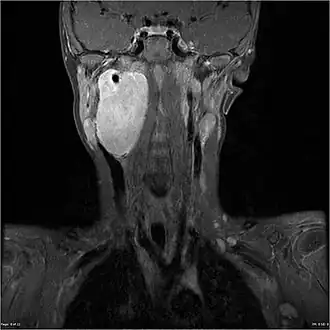

IRM d'un ganglioneuroblastome situé au niveau de la tête et du cou d'un garçon de 7 ans caucasien